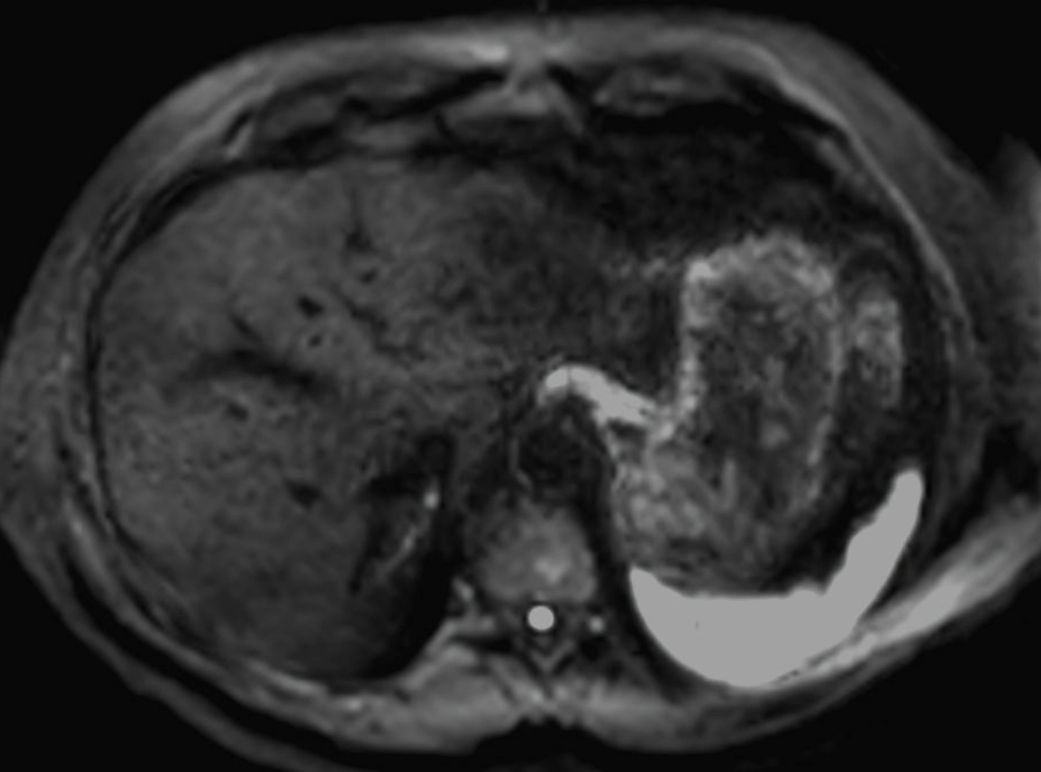

Axial DWI (b0)SmartSpeed Diffusion